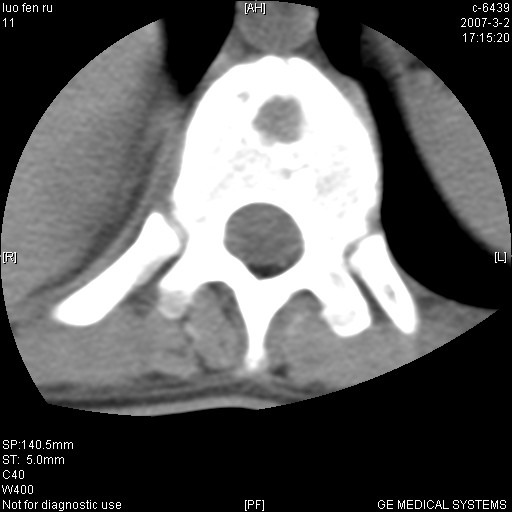

标题: CT6952:T11椎体病变请讨论

女,19岁.背部疼痛一月余.自诉幼时有个外伤史.

腰椎平片示,t11椎体呈楔形改变,椎间隙未见异常.

当是应是椎体(前半部较厉害)压缩性骨折,这就印证了这就是陈旧性骨折。

t11椎体前缘不规则形骨质破坏,周围有硬化边,软组织肿块不明显,首先考虑:骨嗜酸性肉芽肿 。期待随访结果。